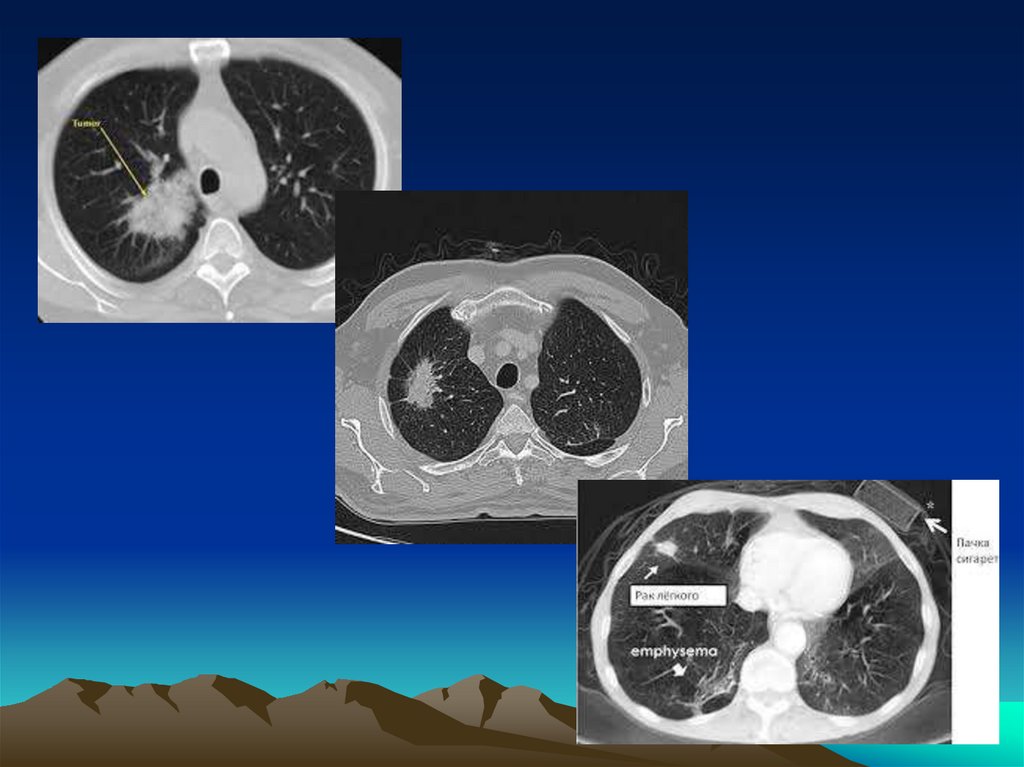

Периферический рак легкого

Боль в груди

Кашель

Одышка

Клиника абсцесса легкого (при распаде опухоли).